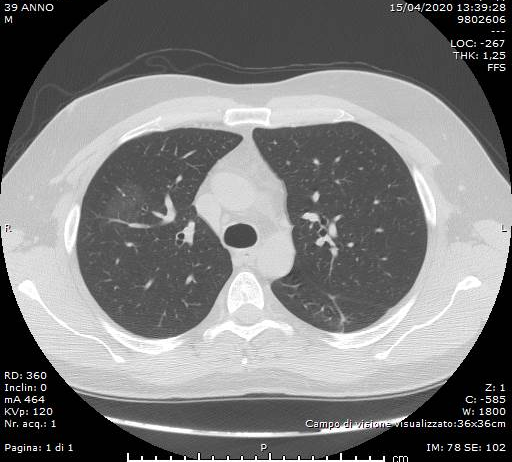

Maschio, 39 anni. Anamnesi patologica remota muta.

Giancarlo GISMONDO VELARDI, Letterio MILITANO, Giuseppe E. GRECO, Ilaria V. TRECROCI, Matilde LICO, Giuseppe CASUSCELLI, Antonino BOVA, Vincenzo FIORILLO, Sandro BALDARI

Dipartimento dei Servizi Sanitari - U.O. Radiologia – ASP Vibo ValentiaMaschio, 47 anni. Anamnesi patologica remota muta.